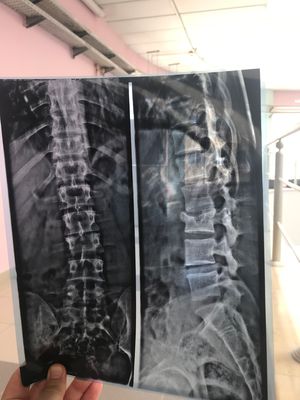

This is the xray photo of my back

Any one knows if i have to make a surgery ? Or not ?? Plz im in a bad situation

I would say surgery to stabilize/decompress😷

You don't have to but you should